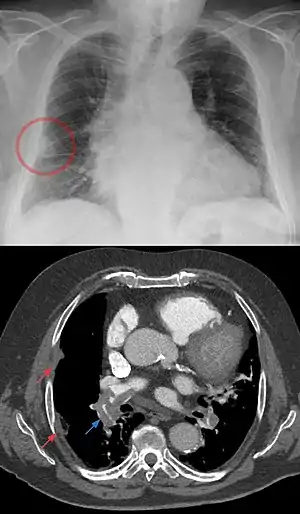

Hampton's hump, also called Hampton hump, is a radiologic sign which consists of a shallow wedge-shaped opacity in the periphery of the lung with its base against the pleural surface. It is named after Aubrey Otis Hampton, who first described it in 1940.[1] Hampton's hump along with Westermark sign may aid in the diagnosis of pulmonary embolism, although they are rare and their sensitivities and interoperator reliabilities are low. If the sign is present in an image, there is a high chance that the person has a pulmonary embolism, but when the sign is absent a pulmonary embolism is not ruled out.

| A Hampton hump in a person with a right low lobe pulmonary embolism shown in CT in the lower image (blue arrow). | |